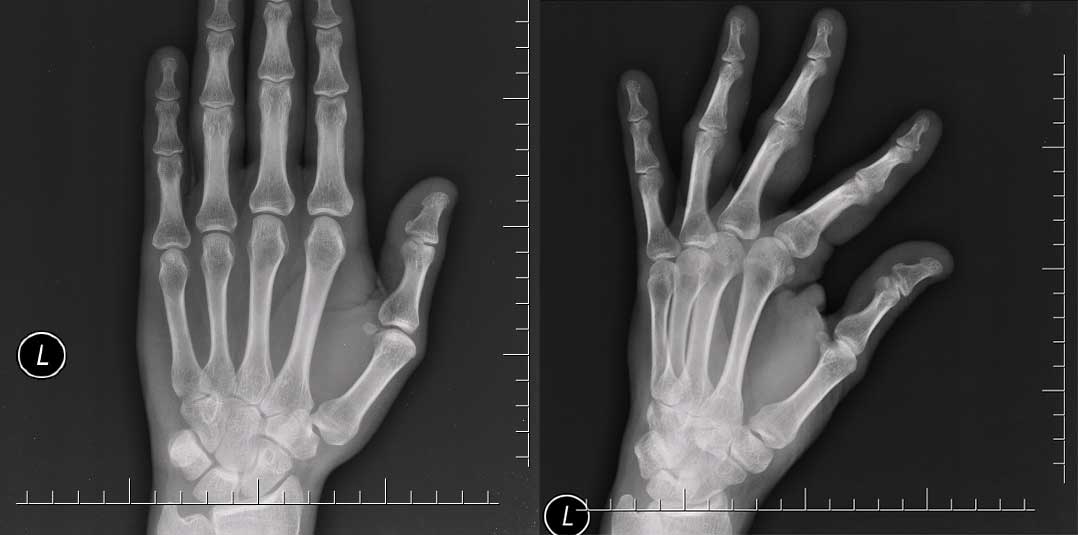

Differing views and differing volumes A case may contain 2D or 3D imaging. In both examples, often more than one view is necessary to assess what's happening. For example, the x-ray of a hand may only reveal a fracture when the hand is in certain pose or angle. Nonetheless it is standard to capture a frontal view of the hand anyways:

A small fracture at the base of the 3rd and 4th middle phalanx is mostly only visible on the right image.